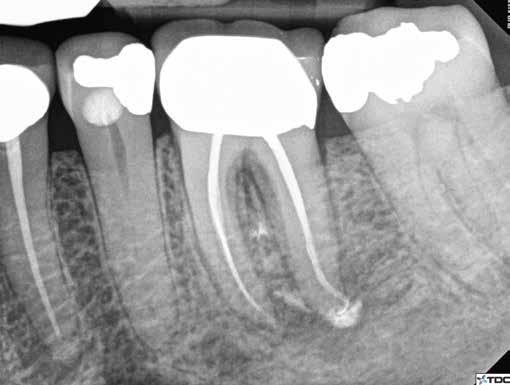

1. a-n. ábrák: Preoperatív CBCT-felvétel a bal alsó 6-os (3.6) fogról. Az axialis (a), coronalis (b) és sagittalis (c) nézeteken a mezialis és distalis gyökerek apicalis harmada körül sugáráteresztő zóna és ép buccalis corticalis csont látható. Egy olyan sablont terveztünk, amely jelezte a csontablak határait az apicalis terület pontos elérése érdekében (d). A mikrosebészeti bevatkozás során a sablont a helyére illesztettük (e), a csontablak határait megjelöltük (f) egy Piezotome CUBE LED kézi-darabba fogott fűrésszel, majd kivágtuk és eltávolítottuk (g és h) az apicalis területhez történő hozzáférés, illetve a mezialis és distalis gyökerek rezekciójának, retrográd preparációjának és retrográd gyökértömésének elvégzése érdekében (i). Végezetül a csontablakot visszaillesztettük és kollagén szivaccsal stabilizáltuk (j). A műtét után közvetlenül készített röntgenfelvétel a 3.6-os fogról (k). A kétéves kontroll során készített CBCT-felvétel: axialis (l), coronalis (m) és sagittalis (n) nézetek.

Egy 63 éves páciens korábban már kezelt bal alsó első nagyőrlőfogából (3.6) eredő mérsékelt fájdalom miatt kereste fel rendelőnket. A kórtörténetében panasza szempontjából releváns információ nem szerepelt. Az elkészült CBCT-felvételen a korábbi kezelések során észre nem vett, jelenleg feltáratlan meziobuccalis csatornát, valamint a mezialis és distalis gyökerek körül kialakult periapicalis elváltozást, és ezt a léziót borító intakt buccalis corticalis csontlemezt láttunk.

Klinikai vizsgálat során vertikális kopogtatási érzékenységet jelzett. A fog körül mérhető szondázási mélység és a fogmobilitás fiziológiás volt. A CBCT-felvételen nem észleltünk a csontos regeneráció megindulására utaló jeleket (1. a–c. ábrák). A korábban gyökérkezelt, gyökértömött és revideált 3.6-os fog esetében az alábbi diagnózis került felállításra: periodontitis periapicalis symptomatica. A panaszokat okozó fog további ellátása során navigált endodonciai mikrosebészetet kívántunk alkalmazni. Az alsó állcsontról intraorális szkent (TRIOS, 3Shape) készítettünk, és a felszíni topográfiát tartalmazó STL fájlt, valamint a CBCT-felvétel készítése során nyert DICOM fájlokat a Blue Sky Bio szoftver segítségével egyesítettük. A sebészi sablon megtervezésére az így kapott háromdimenziós képet használtuk. A sablon kialakítása során arra törekedtünk, hogy a sablon egyértelműen meghatározza a gyökércsúcsi terület eléréséhez szükséges csontablak határait (1. d. ábra)